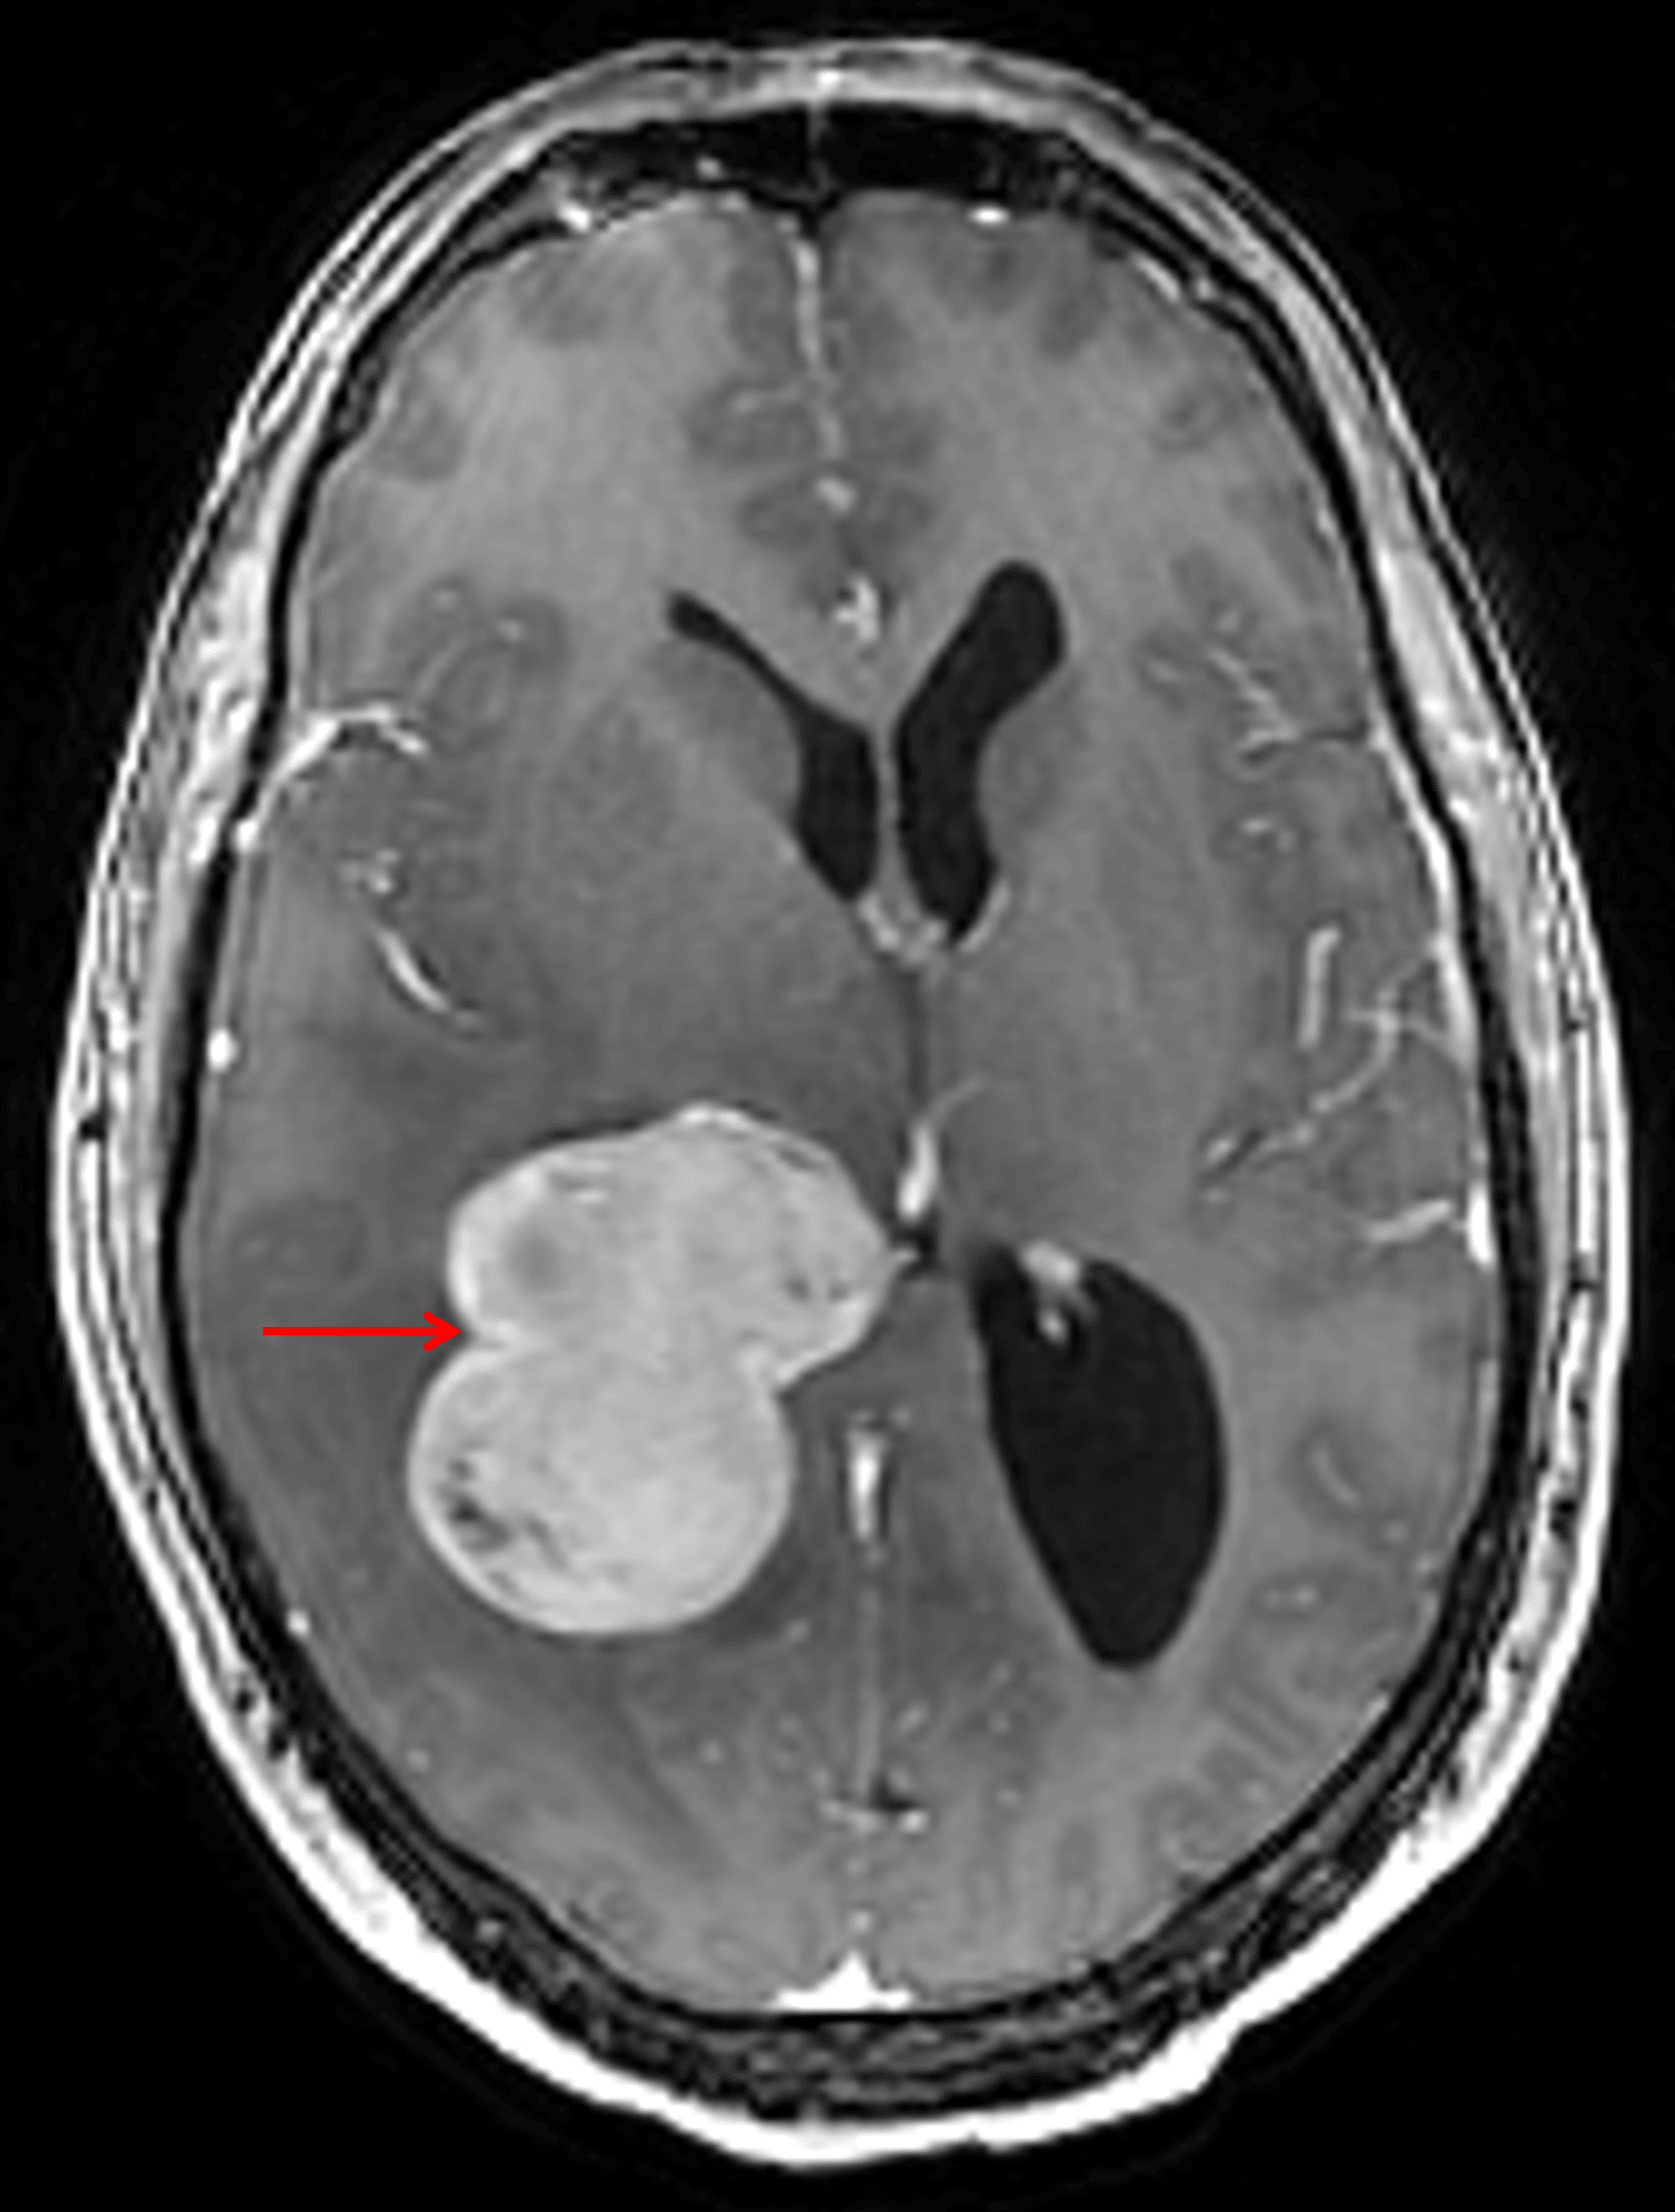

• Homogeneously enhancing mass with lobulated contours centered in the atrium of the right lateral ventricle measuring 5.5 x 4.8 x 3.7 cm

Homogeneously enhancing mass centered in the atrium of the right lateral ventricle (red arrow).